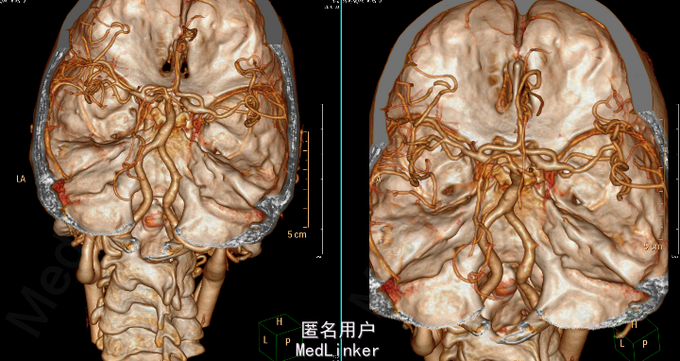

查体:T 37.0℃,P 82bpm,R 20bpm,BP 180/109mmHg。 专科情况:意识模糊,自主睁眼,无法言语,呼之不应,不配合检查。颈软;无强迫头位。眼裂对称,眼睑无下垂,眼球位置居中,各向活动五受限,未见眼球震颤,双侧瞳孔等大等圆,对光反射灵敏。双侧额纹对称,右侧鼻唇沟变浅。混合性失语,饮水呛咳。四肢肌肉萎缩,四肢肌张力增高,疼痛刺激后右上肢肌力1级,右下肢肌力2级,左侧肢体肌力2级。双侧Babinski征、Chaddock征阳性。 辅助检查:2015-06-03外院头颅MR:1.左侧额顶叶急性脑梗死;2.右侧颞枕叶、小脑、双侧基底节区及脑桥软化灶;3.脑白质缺血,脑萎缩。 2015-06-25我院头颅CTA:1.右侧小脑半球、右侧枕叶、双侧基底节区、放射冠及半卵圆中心多发缺血、梗死、软化灶;脑白质变性;脑萎缩。2.基底动脉延长、扩张,双侧椎动脉颅内段扩张(基底动脉管径最大约6mm,末端超出鞍背范围;右侧椎动脉颅内段管径最大约5mm,左侧椎动脉颅内段管径最大约4.5mm),考虑椎-基底动脉延长扩张症。3.脑动脉硬化;左侧大脑前动脉A2段闭塞;右侧颈内动脉海绵窦段、右侧大脑前动脉A2段、左侧大脑后动脉局限性狭窄;右侧颈内动脉海绵窦段钙化斑块;右侧大脑后动脉汇入右侧颈内动脉,考虑先天变异。

椎基底动脉延长扩张症(VBD) 是指椎基底动脉显著延长、扭曲并伴有管径增粗,因异常的血管搏动可致小脑功能障碍、脑梗死(BI)、脑干受压等症状。VBD 是一种少见的、病因尚未明确的全身血管广泛性病变,可同时累及微小穿支血管,其发病率较低,但各研究所报道的发病率差异较大,可能与其选择的研究人群类型不同有关。此外研究已证实,VBD危险因素有男性、高血压、吸烟、酗酒、CVD 家族史,其发病高峰主要分布在60~80岁,且更易引起缺血症状。VBD 是脑卒中的独立危险因素,对伴或未伴有VBD的脑卒中患者进行的比较研究发现高血压、VBD 形态学改变的严重程度及其影像学进展可促进VBD 患者脑梗死及脑出血的发生,BA 直径越大、水平移位越严重与脑出血越密切相关,而BA延长的程度与脑干受压、动脉瘤的类型及BA最初的最大直径呈正相关。有学者认为VBD与椎基底动脉内弹力膜的广泛缺陷及中膜网状纤维的缺乏有关。由于VBD导致血流动力学改变和对脑干及颅神经的压迫使其临床表现差异较大,其临床表现可归纳为以下4种:(1)脑神经及脑干压迫症状;(2)椎基底动脉供血不足及梗死;(3)脑出血;(4)脑积水。VBD的影像学诊断标准VBD 的影像学诊断标准, 基底动脉(BA) 或椎动脉(VA) 直径≥4.5mm,或侧方移位>10mm,且BA 全长> 29.5mm 或颅内段长度> 23.5mm。